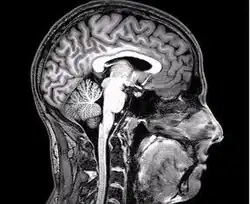

Magnetická rezonance

Metoda využívá magnetické vlastnosti některých prvků, respektive jejich jader. Magnetická rezonance poskytuje vyšší rozlišení než rentgen či počítačová tomografie. Lze použít i kontrastní látku, které pomáhá odhalit záněty či nádorové tkáně. Magnetická rezonance umožnila neinvazivní vyšetření některých orgánů. Další výhodou je absence škodlivého ionizujícího záření. Nevýhodou magnetické rezonance je jednak poměrně dlouhé a hlučné vyšetření, ale i vysoké pořizovací náklady. Problematické je vyšetření i pro pacienty s kovovými předměty v těle (naslouchadla, kardiostimulátory) či tetováním.